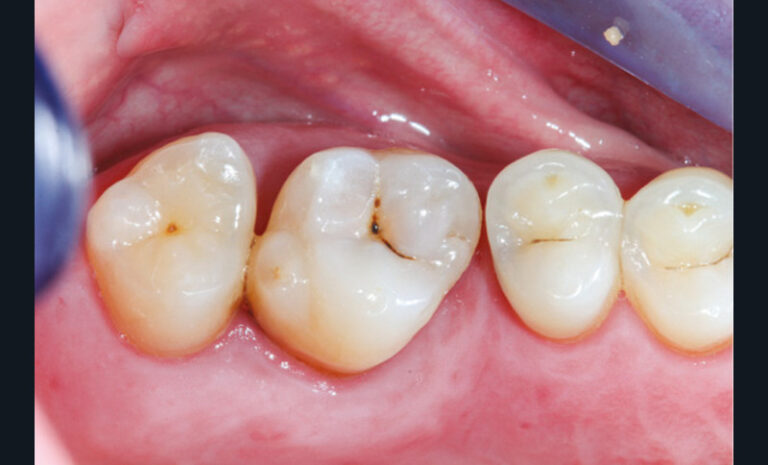

Cette version, quand elle se produit, modifie les espaces interdentaires et complique l’hygiène proximale des patients. Des caries peuvent alors se développer en interproximal sans que cela soit forcément visible à l’examen visuel (fig. 3 et 4). Les radios de type bite-wing (rétro-coronaires) prennent alors tout leur sens (fig. 5 et 6).